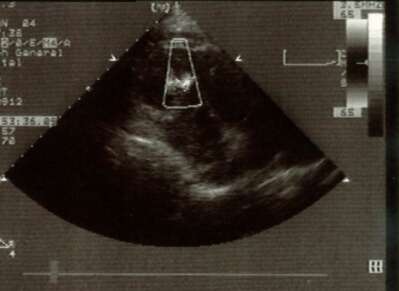

Clinical diagnosis of the acute ventricular septal rupture was confirmed by an emergent echocardiogram (panel below) which showed akinesis of the anterior wall and septum and abnormal flow across the distal part of the ventricular septum directed from left-to-right.

Echocardiogram